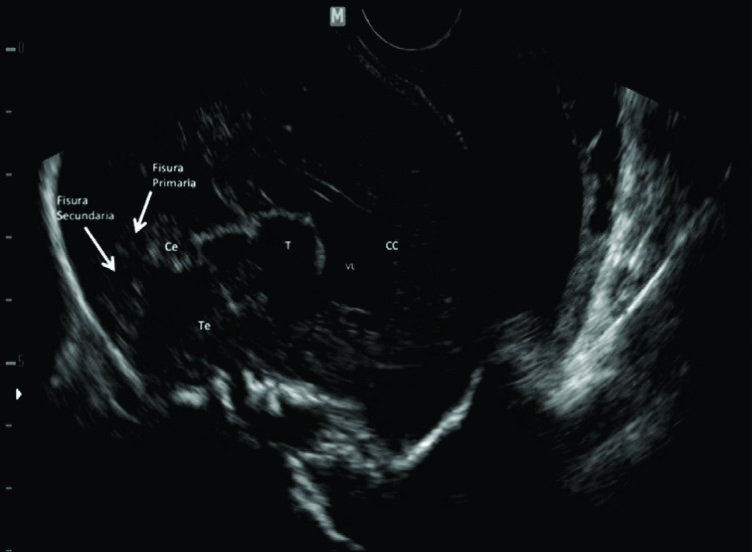

Figura 12

NSF, Anatomía Normal de línea media.

Estudio dirigido de ecografía para analizar el sistema nervioso, corte sagital para evaluar las estructuras de línea media (29 semanas de gestación). En la imagen seleccionada se observa la anatomía de las estructuras supra e infra-tentoriales con excelente precisión. Se observa el cuerpo calloso (CC) y parte de los ventrículos laterales (VL). El tronco encefálico (Te) y cerebelo (Ce) se distinguen claramente con el IV ventrículo ubicado entre ellos. En el Ce se identifican claramente las fisuras primaria y secundaria.

T: Tálamo